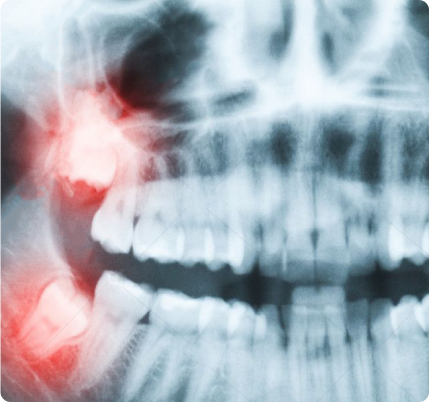

As with any dental procedure, your dentist will want to initially conduct a thorough examination of the wisdom and surrounding teeth. Panoramic or digital x-rays will be taken in order for your dentist to evaluate the position of the wisdom teeth and determine if a current problem exists, or the likelihood of any potential future problems. The x-rays can also expose additional risk factors, such as deterioration or decay of nearby teeth. Early evaluation and treatment (typically in the mid-teen years) is recommended in order to identify potential problems and to improve the results for patients requiring wisdom teeth extractions. Only after a thorough examination can your dentist provide you with the best options for your particular case.

In most cases, inadequate space in the mouth does not allow the wisdom teeth to erupt properly and become fully functional. When this happens, the tooth can become impacted (stuck) in an undesirable or potentially harmful position. If left untreated, impacted wisdom teeth can contribute to infection, damage to other teeth, and possibly cysts or tumors.

There are several types, or degrees, of impaction based on the actual depth of the teeth within the jaw:

Soft Tissue Impaction: The upper portion of the tooth (the crown) has penetrated through the bone, but the gingiva (gum) is covering part or all of the tooth’s crown and has not positioned properly around the tooth. Because it is difficult to keep the area clean, food can become trapped below the gum and cause an infection and/or tooth decay, resulting in pain and swelling.

Partial Bony Impaction: The tooth has partially erupted, but a portion of the crown remains submerged below the gum and surrounding jawbone. Again, because it is difficult to keep the area clean, infection will commonly occur.

Complete Bony Impaction: The tooth is completely encased by jawbone. This will require more complex removal techniques.